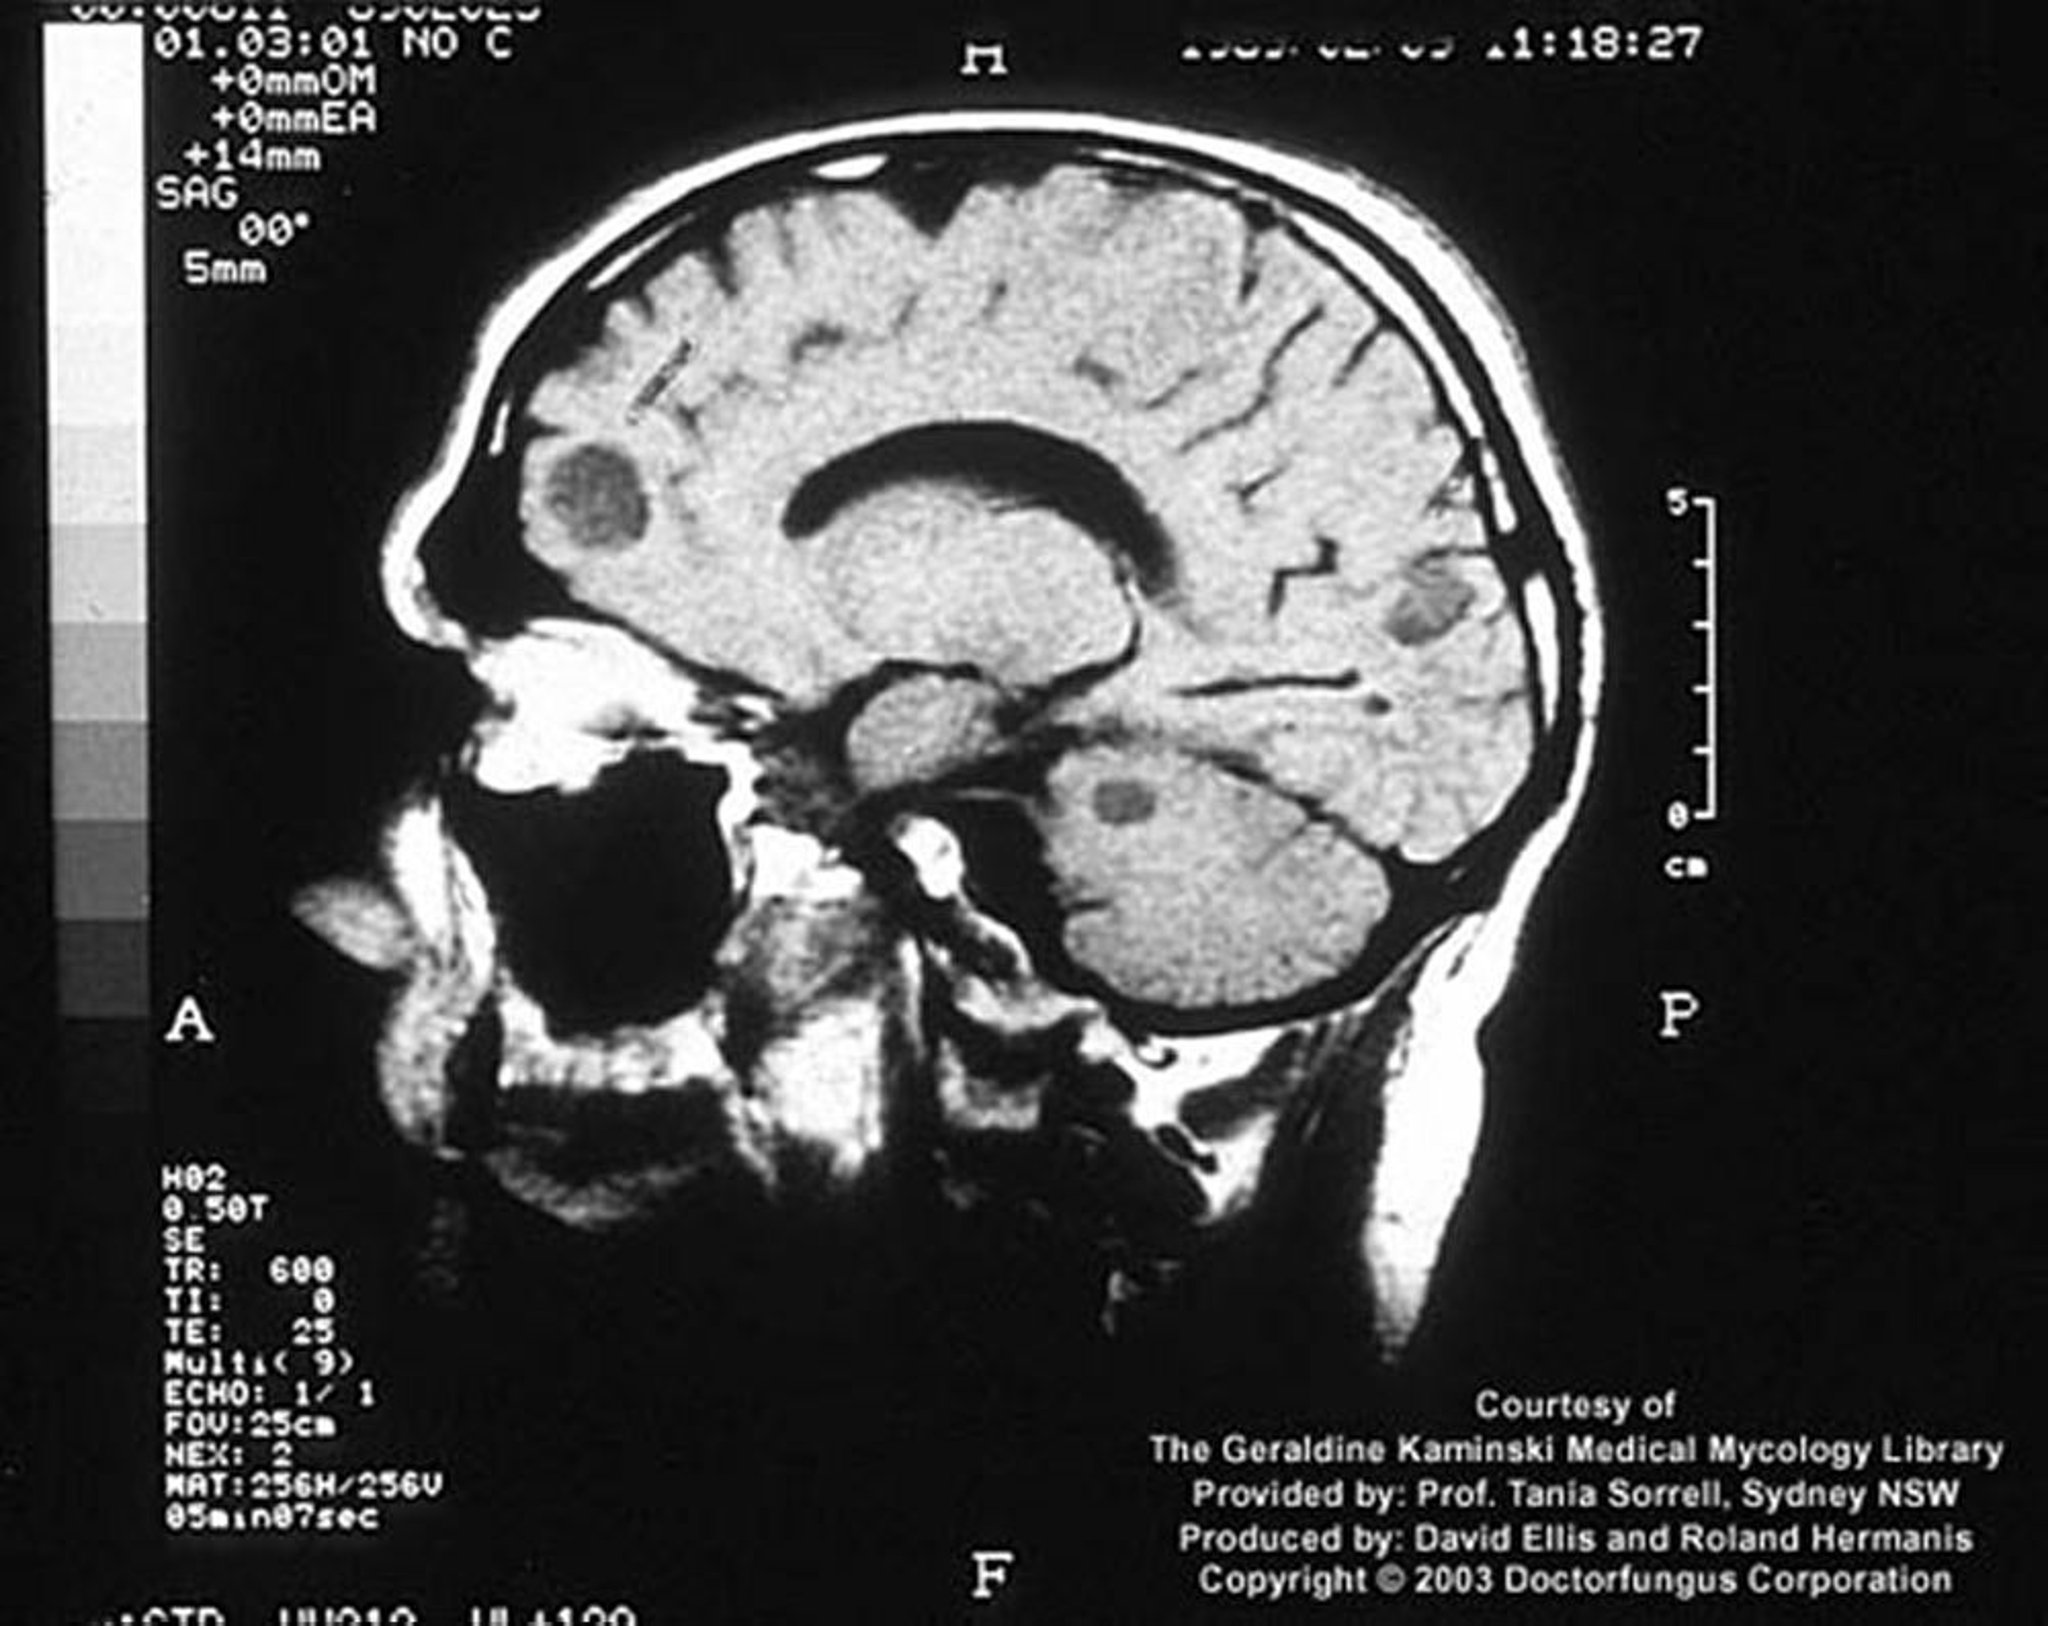

Criptococosis (sistema nervioso central)

En un huésped inmunocomprometido, la infección criptocócica puede manifestarse como lesiones cerebrales focales llamadas criptococomas.

Image courtesy of www.doctorfungus.org © 2005.